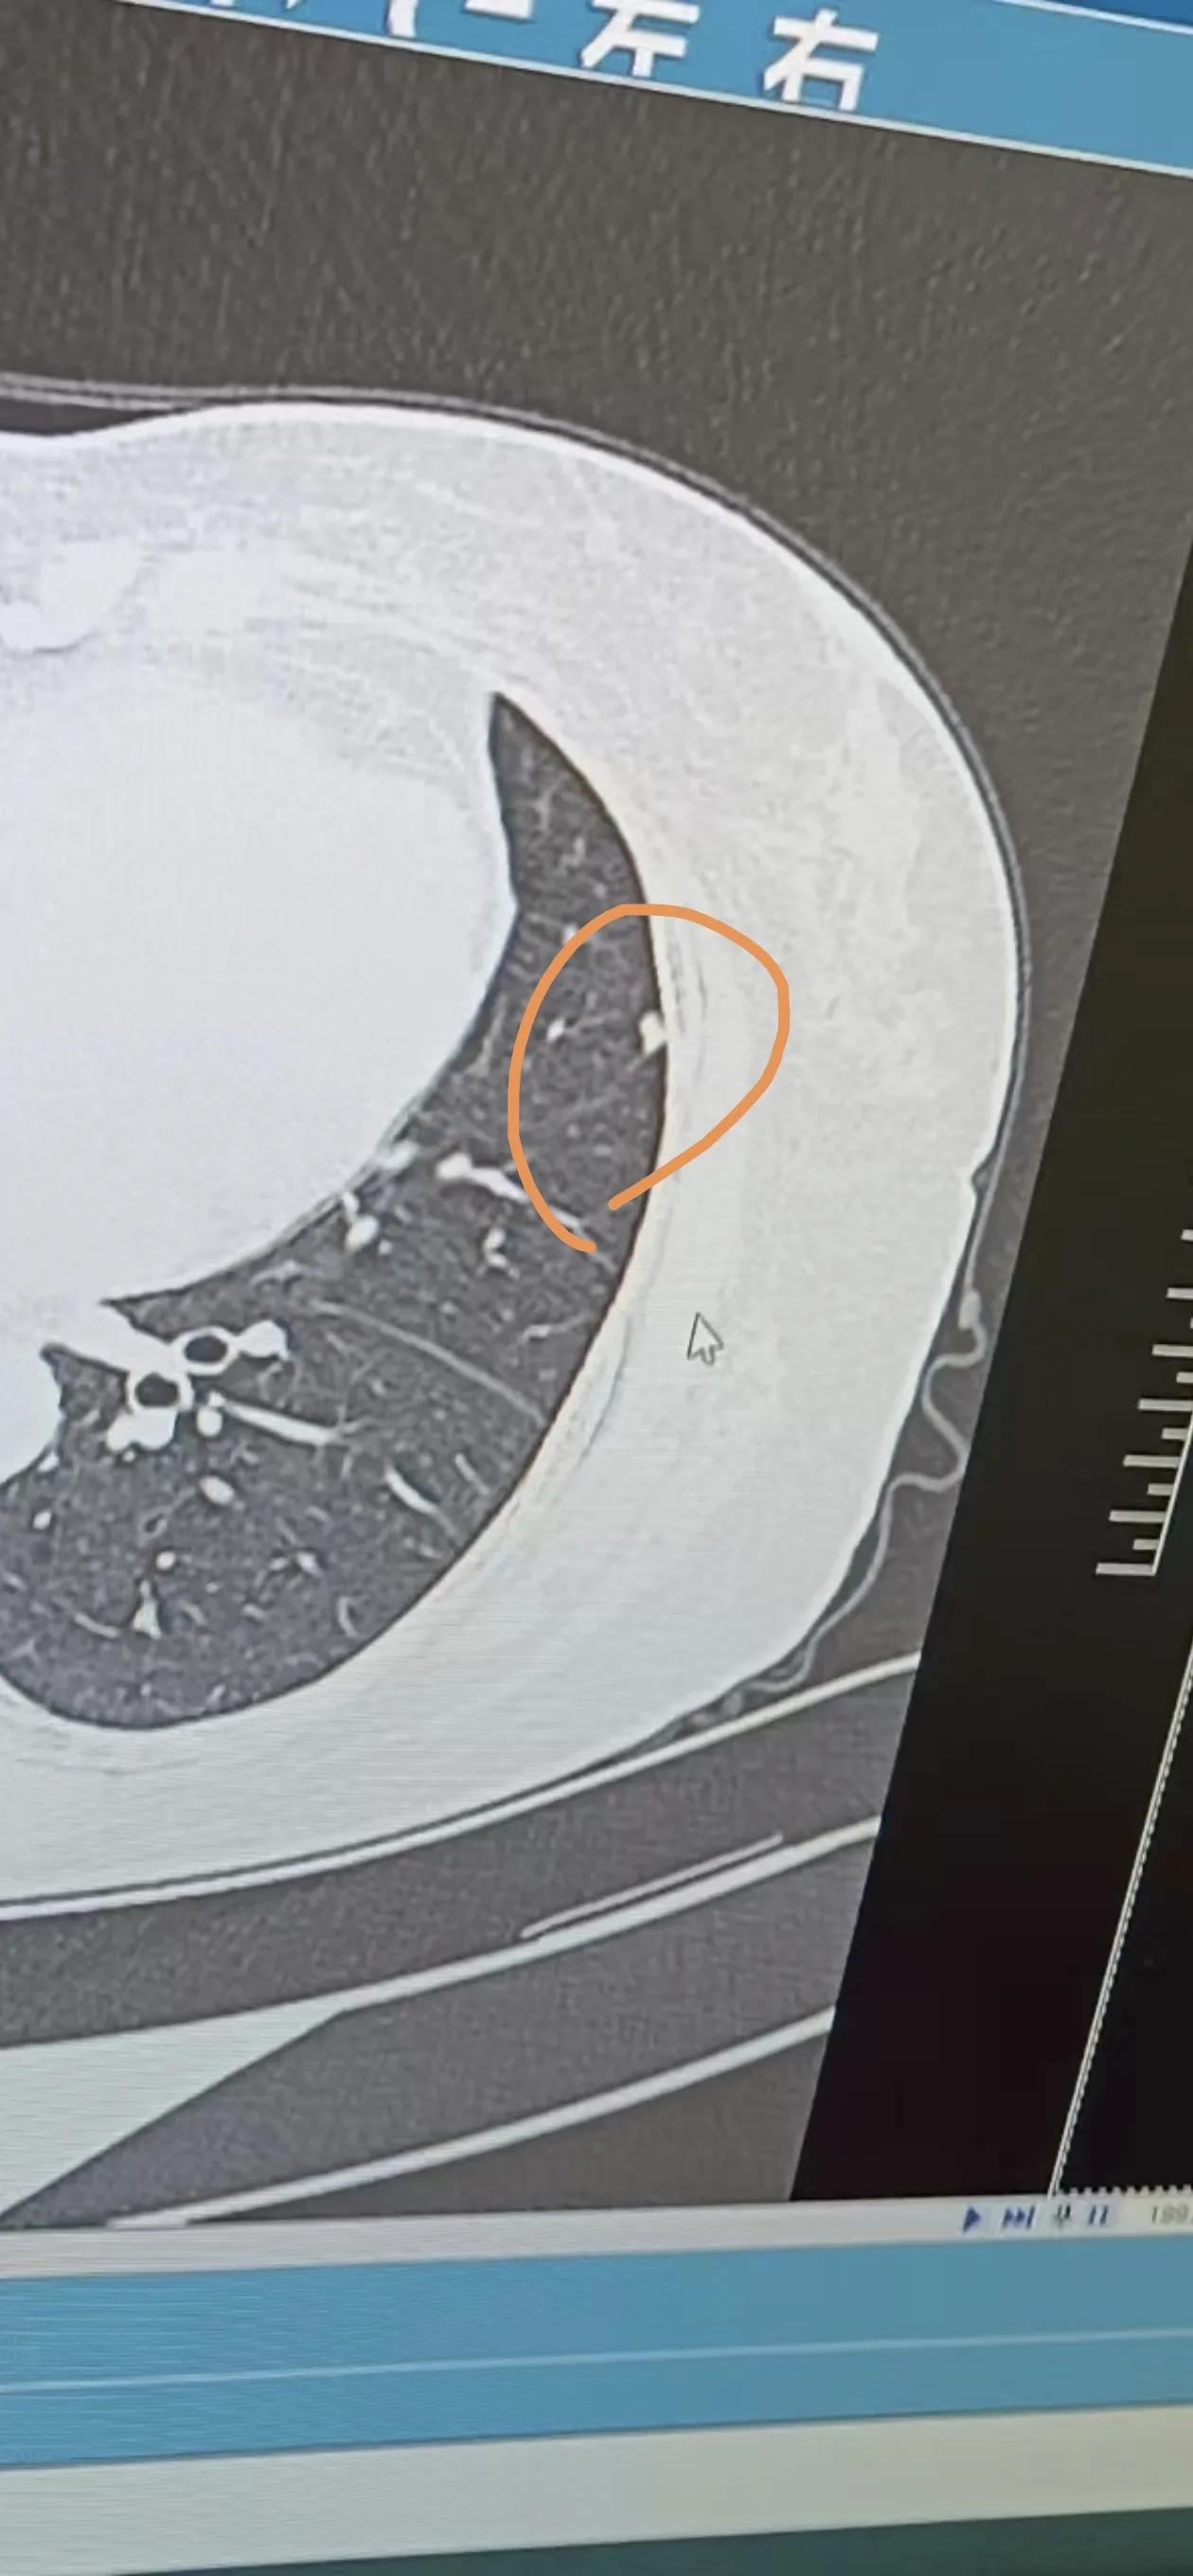

肺结节有毛刺别慌,医生教你读懂这些危险信号

图片尺寸960x1280